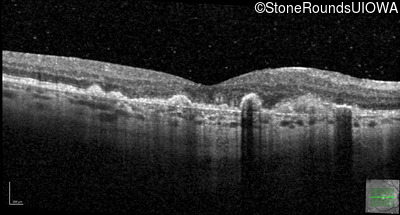

Malattia Leventinese (IIJ)

Malattia Leventinese (IIJ)

This 43 year old woman has experienced a gradual reduction in her central vision for the past 3 years.

| Malattia Leventinese | EFEMP1 | Arg345Trp CGG>TGG | AD |